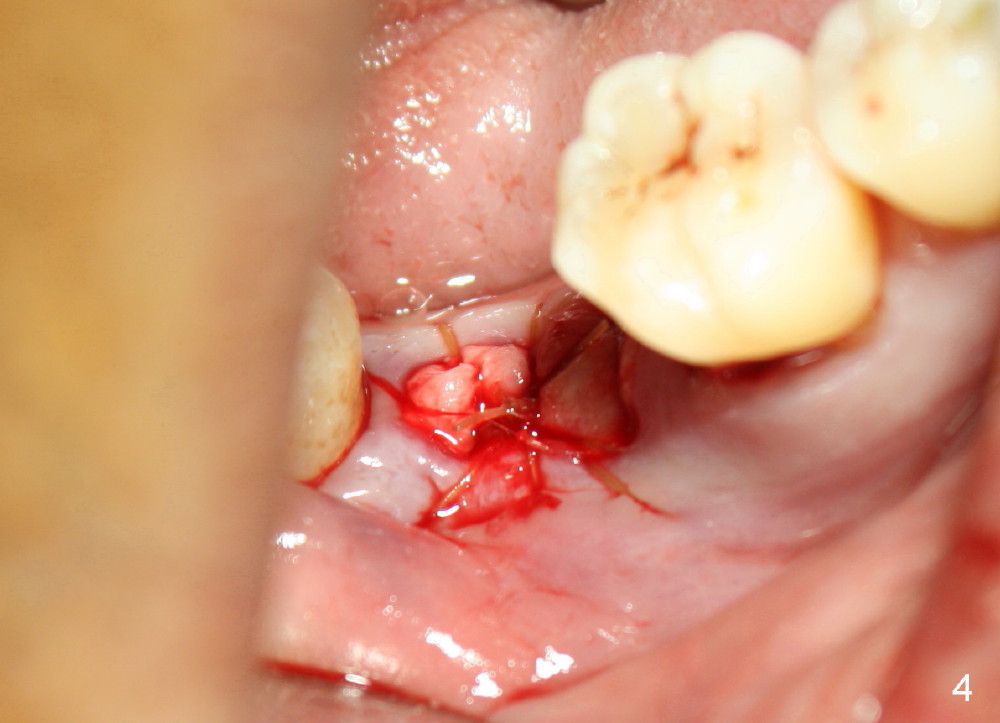

Intraop PA with a radiopaque instrument in the socket reveal the socket is large (Fig.2 arrows). The latter is filled with bone graft (Fig.3 arrows) and collagen plug (Fig.4). Fig.5 and 6 show wound healing 7 and 13 days postop. The ridge is not atrophic 4 months postop (Fig.7), ready for implant.